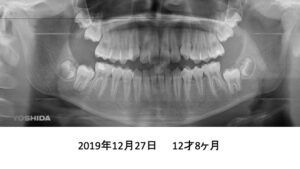

もう1症例、8才4ヶ月の患者さんです。

パノラマでは、永久歯が入るスペースが足りないように見えます。

4年後です。治療は何もしていません。

さらに2年後、全ての歯がちゃんと萌出しました。